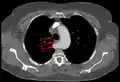

Artère sous-clavière aberrante au scanner axial. (1) trachée, (2) œsophage, (3) Artère sous-clavière aberrante.